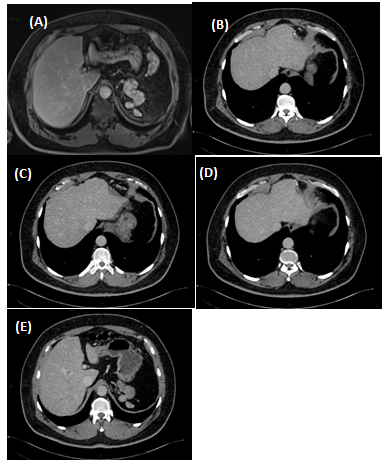

Male, 47years old with an incidental finding of hepatic lesion, during investigation of nephrolithiasis. Previous history of splenectomy after abdominal trauma due to automobile accident 20years ago. Hypertensive in use Olmesartan. Denied other pathologies and surgeries. On physical examination: good general condition, anicteric, painless abdomen, without palpable masses. Laboratory tests: Hb 14g/dL (13,5- 17,5), Hct 44,4% (39-55), Platelets 268,000/mm3 (150.000 - 400.000), creatine 0,9mg/dL (1,5), INR 0,8, CEA 1,33ng/mL (<3,0), CA 19-9 20U/mL (<37), AFP 1,5ng/dl (<7,22 ), albumin 4,19g/dL (3,4- 4,8), AST 20U/L (17-55), ALT 18U/L (21-71), GGT 54U/L (15/73), AP 48U/L (38-126), total bilirrubin 0,57mg/dL (0,2-1,3). MRI showed nodular hepatic lesion, 42x41x28mm, slight hyperintense in T2, with contrast enhancement and washout in late phase, in segment II, without dilatation of biliary tract (Figures 1). The initial diagnosis was hepatic adenoma. Proceeded with hepatic segmentectomy, with good evolution. The surgical specimen referred to pathological anatomy and revealed hepatic splenosis (Figures 2 & 3).

Figure 2 Postoperative figures A, B, C, D and E. Computed Tomography (CT). Postoperative CT in the axial plane in the post-contrast venous phase show signs of partial resection of the liver segment II (A,B, C and D), as well as splenectomy with small implants of splenic tissue in the left subphrenic region (E).

Intrahepatic splenosis shows increased enhancement on CT or MR images during the arterial phase. Performing gadoxetic acid–enhanced hepatocyte-phase MR imaging does not help because intrahepatic splenosis is hypointense during the hepatospecific phase. The MR technique involving administration of small iron oxide particles (SPIO-Endorem), which is taken up by liver and spleen reticuloendothelial cells, has proven to be effective in differentiating intra-hepatic splenosis from other lesions.13,14,17 With SPIO (superparamagnetic iron oxide) intrahepatic splenic nodes remain hyperintense.18 Noncontrast CT reveals a well circumscribed iso- or hypodense mass in the liver, while noncontrast MRI demonstrates mild-to-moderate hyperintensity on T2-weighted image and hypointensity on the T1-weighted image. A dynamic study on CT and MRI shows a slight to intense enhancement, which may be homogeneous or heterogeneous during the arterial phase but enhancement is diversely during the portal venous and equilibrium phases in different cases. Compared with the surrounding hepatic parenchyma, the lesion could reveal hypodensity and hypointensity, or hyperdensity in the arterial phase. Or it can demonstrate diminished enhancement, slight enhancement, or increased enhancement during the following phases (Figures 1 & 2).18,19